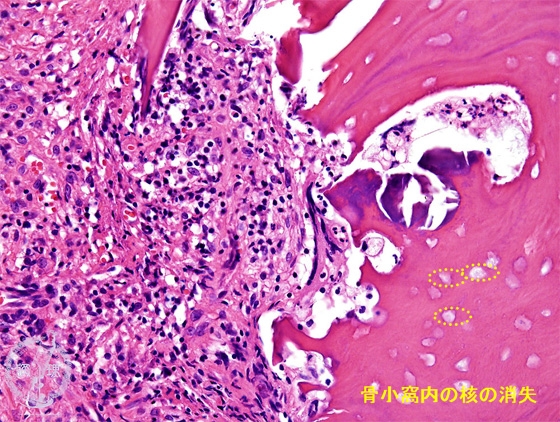

- (5)Suppurative osteomyelitis

Microscopic view (HE: high power view):Infiltration of neutrophils and fibrosis are seen. Bone is necrotic, with disappearance of the nuclei within the lacuna of the bone.